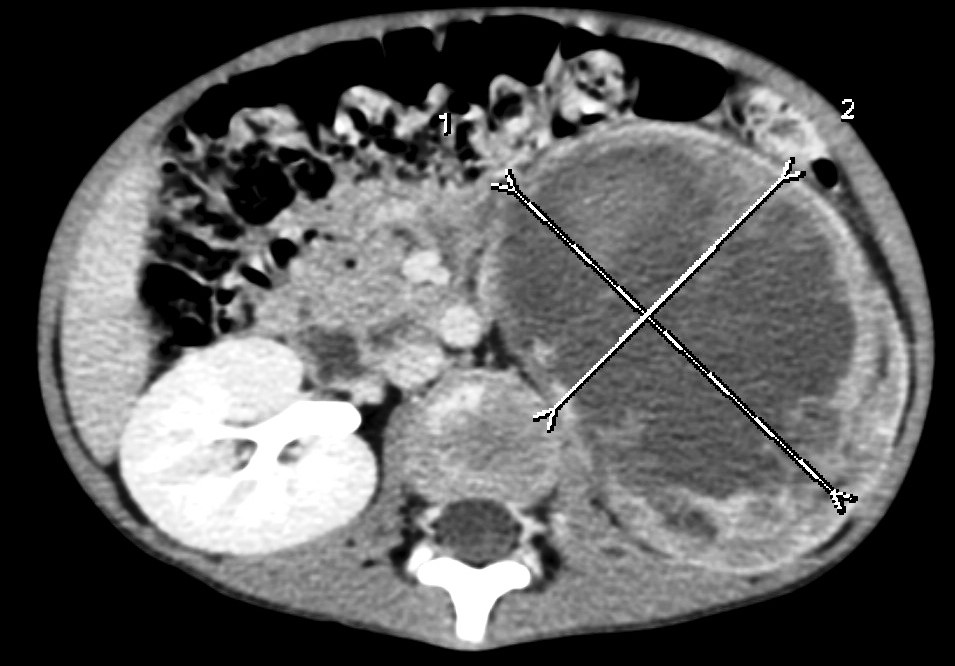

Image

29. CT-examination after iv. contrast administration. Mostly hypodense mass arising from the left kidney. Wilms tumor. (with the courtesy of Dr. Z. Karádi)